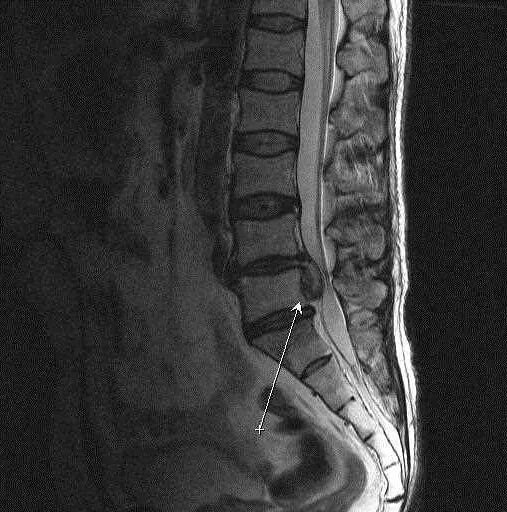

Как выглядит грыжа позвоночника на мрт